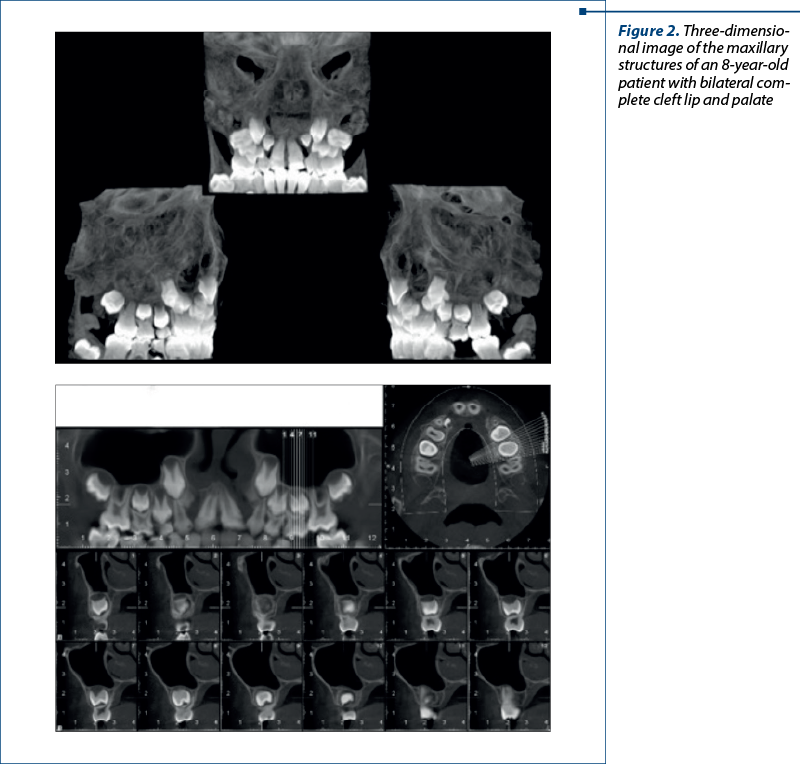

CBCT can also be used to obtain a 3D image of the maxillary structures in order to print an obturator to close oronasal fistulas (Figure 2).